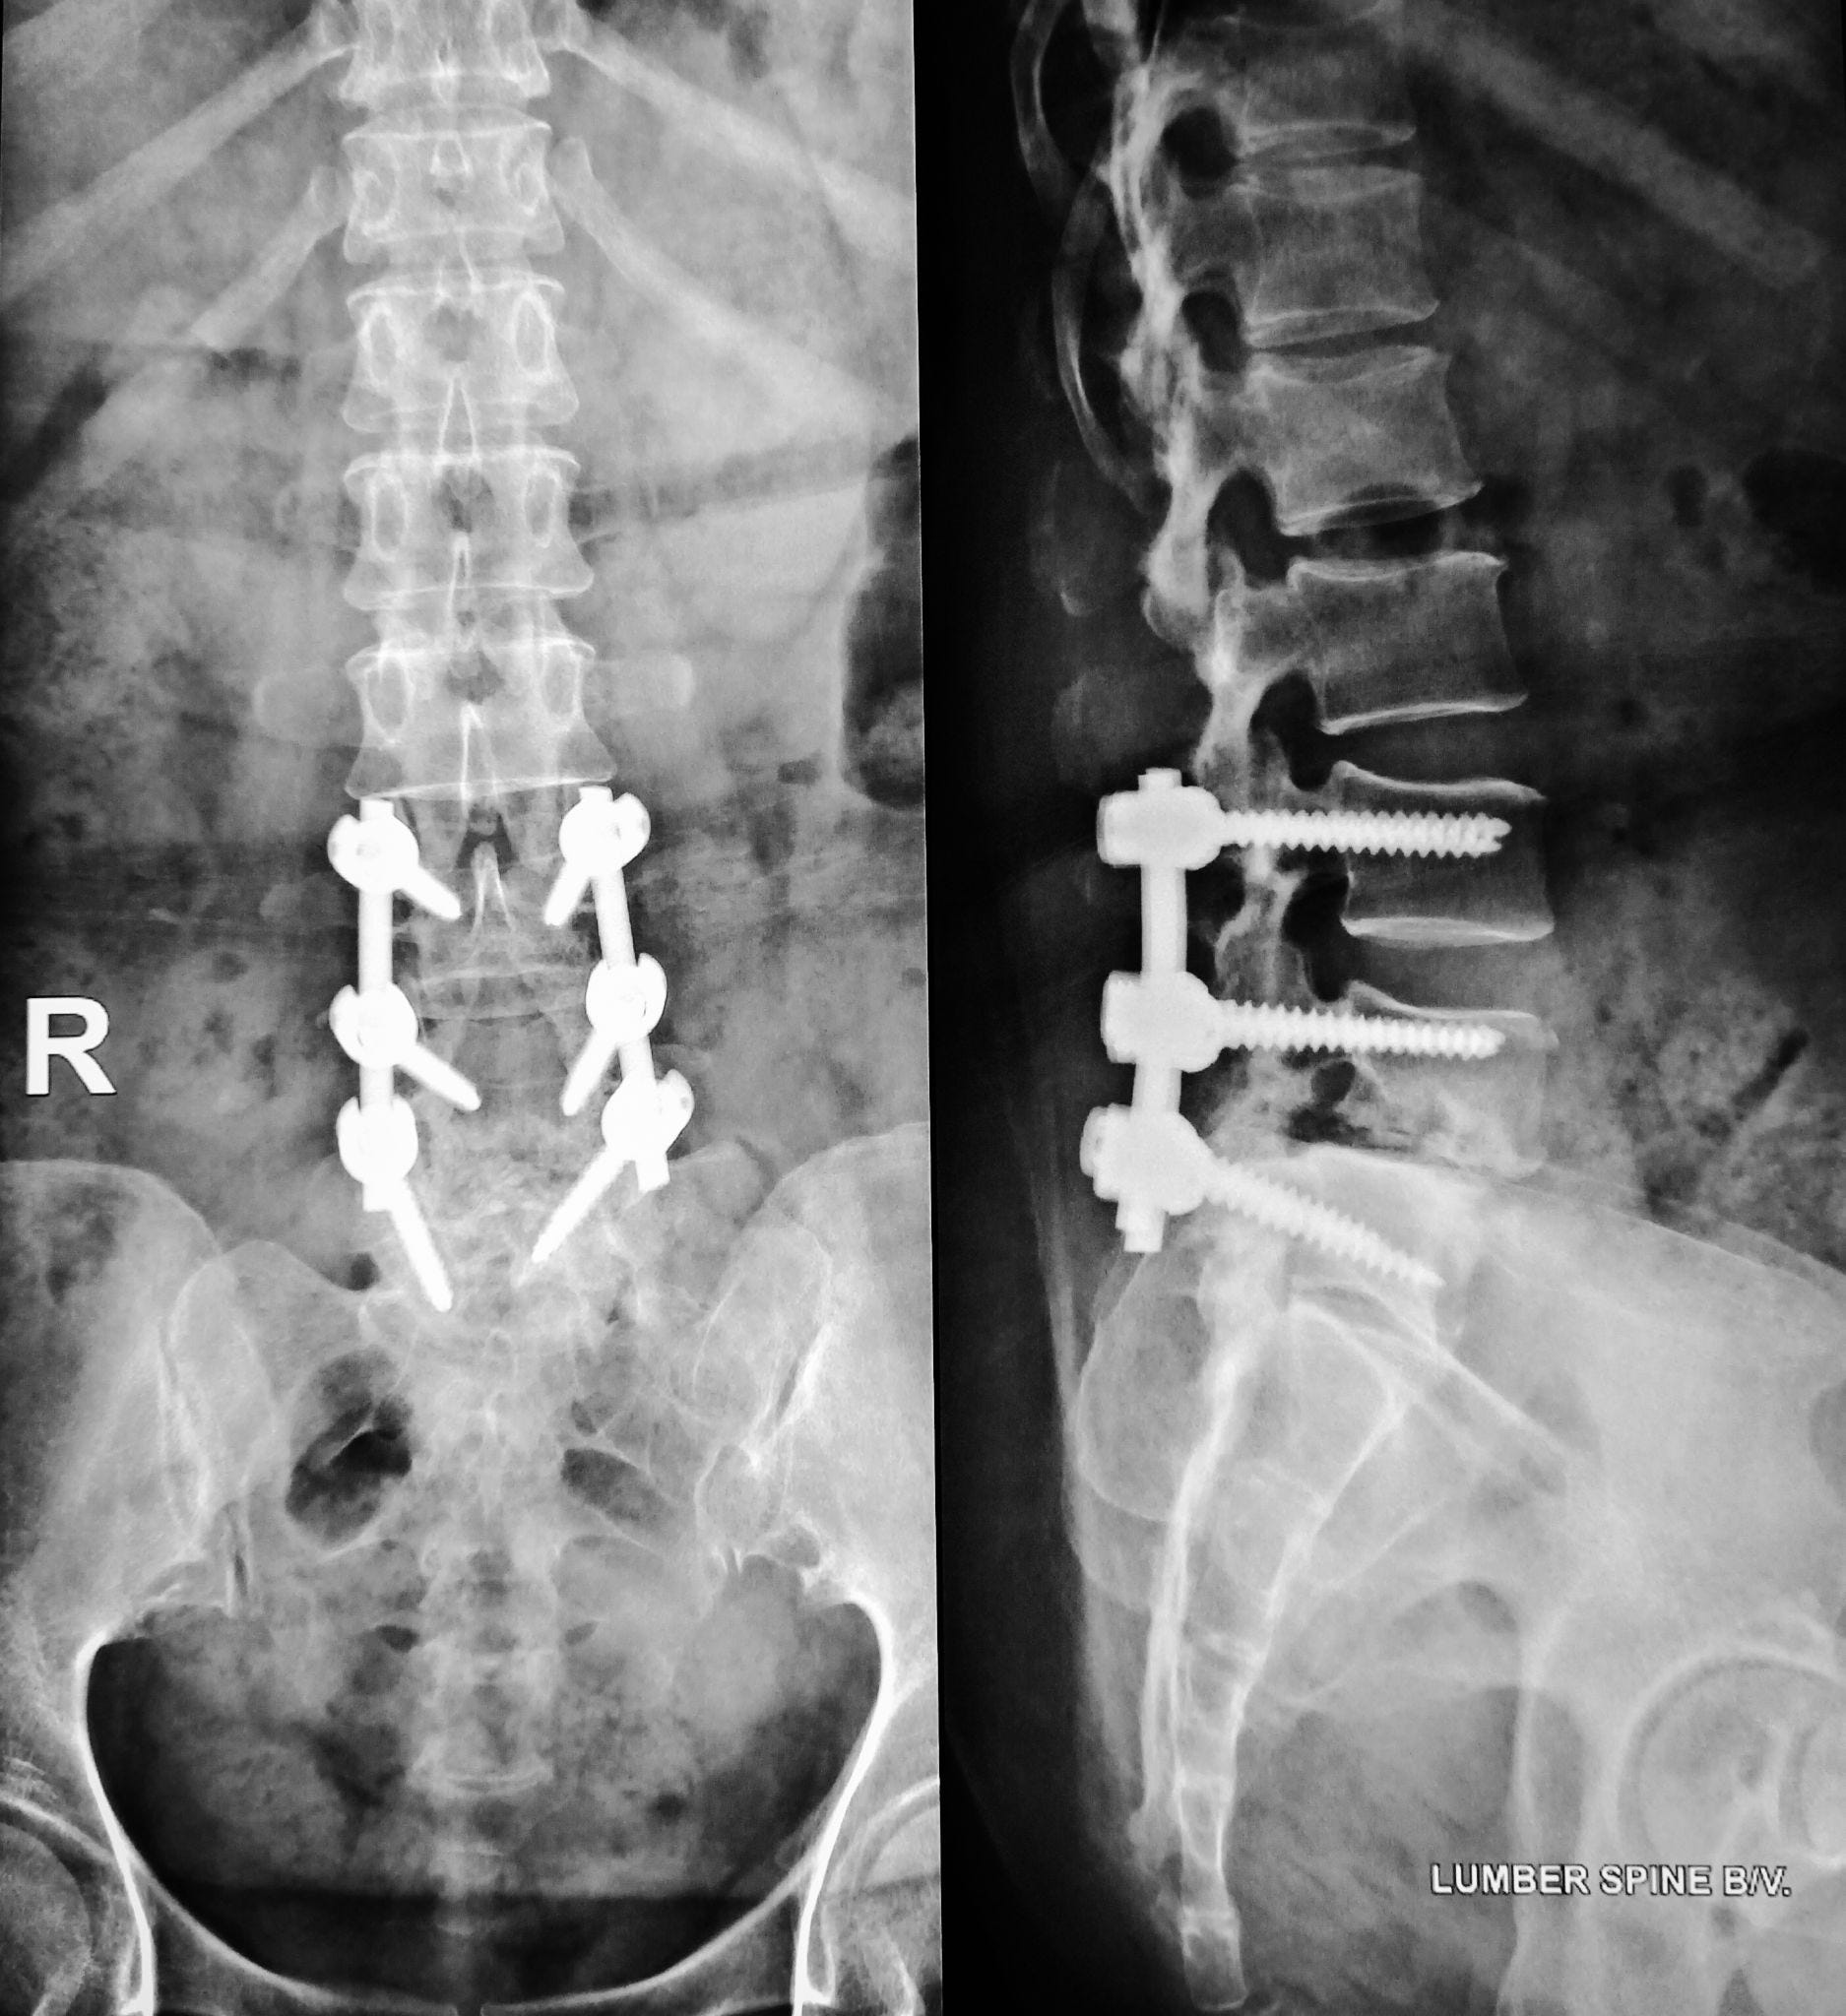

• Fusions and hardware-heavy procedures—the most dangerous and least justified

The long-term risks of fusions are absolutely brutal:

• Loss of mobility

• Adjacent vertebrae breaking down

• Hardware failure

• Repeat surgeries

• Chronic pain

• Nerve injury

• Arachnoiditis

• Metallosis from toxic implant metals